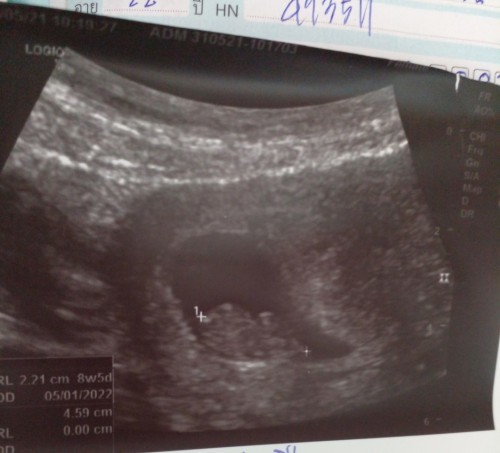

วันนี้ได้เข้าไปอัลตร้าซาวกับหมอสูติได้พบว่ามีถุงตั้งครรภ์แต่ไม่มีตัวอ่อน ถ้านับอายุครรภ์จากปจด.คือ10w.แต่คุณหมอบวกลบท้องลม คุณแม่นัดอีก2อาทิตย์ถ้าไม่เจอตัวอ่อนก็เปนท้องลม หมอบอกอายุครรภ์อาจจะพึ่งได้7w ใครเจอแบบนี้บ้างมั้ยค่ะ เครียดยุค่ะ

หมอคอนเฟิร์มแล้วว่าท้องลม ขอบคุณสำหรับความคิดเห็นจากทุกๆคนค่ะ😥

ตอน8สัปดาห์5วันคะคุณแม่ เจอตัวเเละหัวใจ6สัปดาห์คะ

ภาพนี้ซาวน์ตอน 7week ค่ะแม่เห็นเป็นแบบนี้เเล้ว